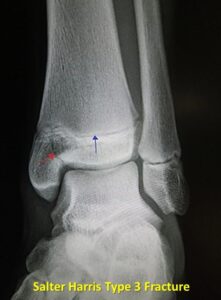

A Salter Harris Type III fracture is an intra-articular fracture that extends from the physis into the epiphysis.